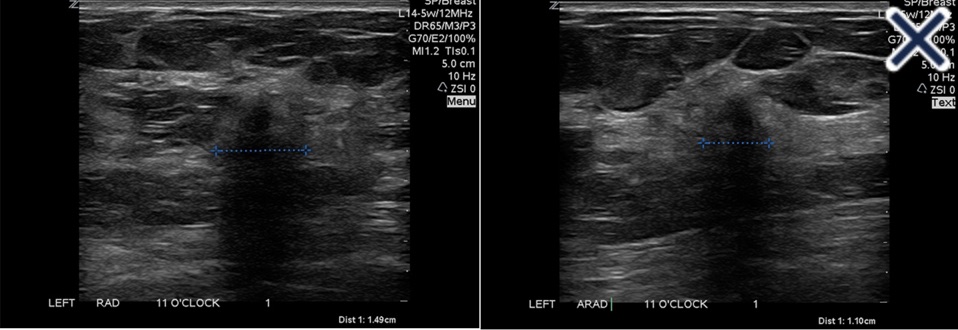

• The suppression of speckle artifact by coded harmonics makes solid nodules more hypoechoic and conspicuous than they are with fundamental imaging (Images a and b)

A. Infiltrating ductal carcinoma with fundamental imaging.

B. The same infiltrating ductal carcinoma as 2a with coded harmonic imaging.